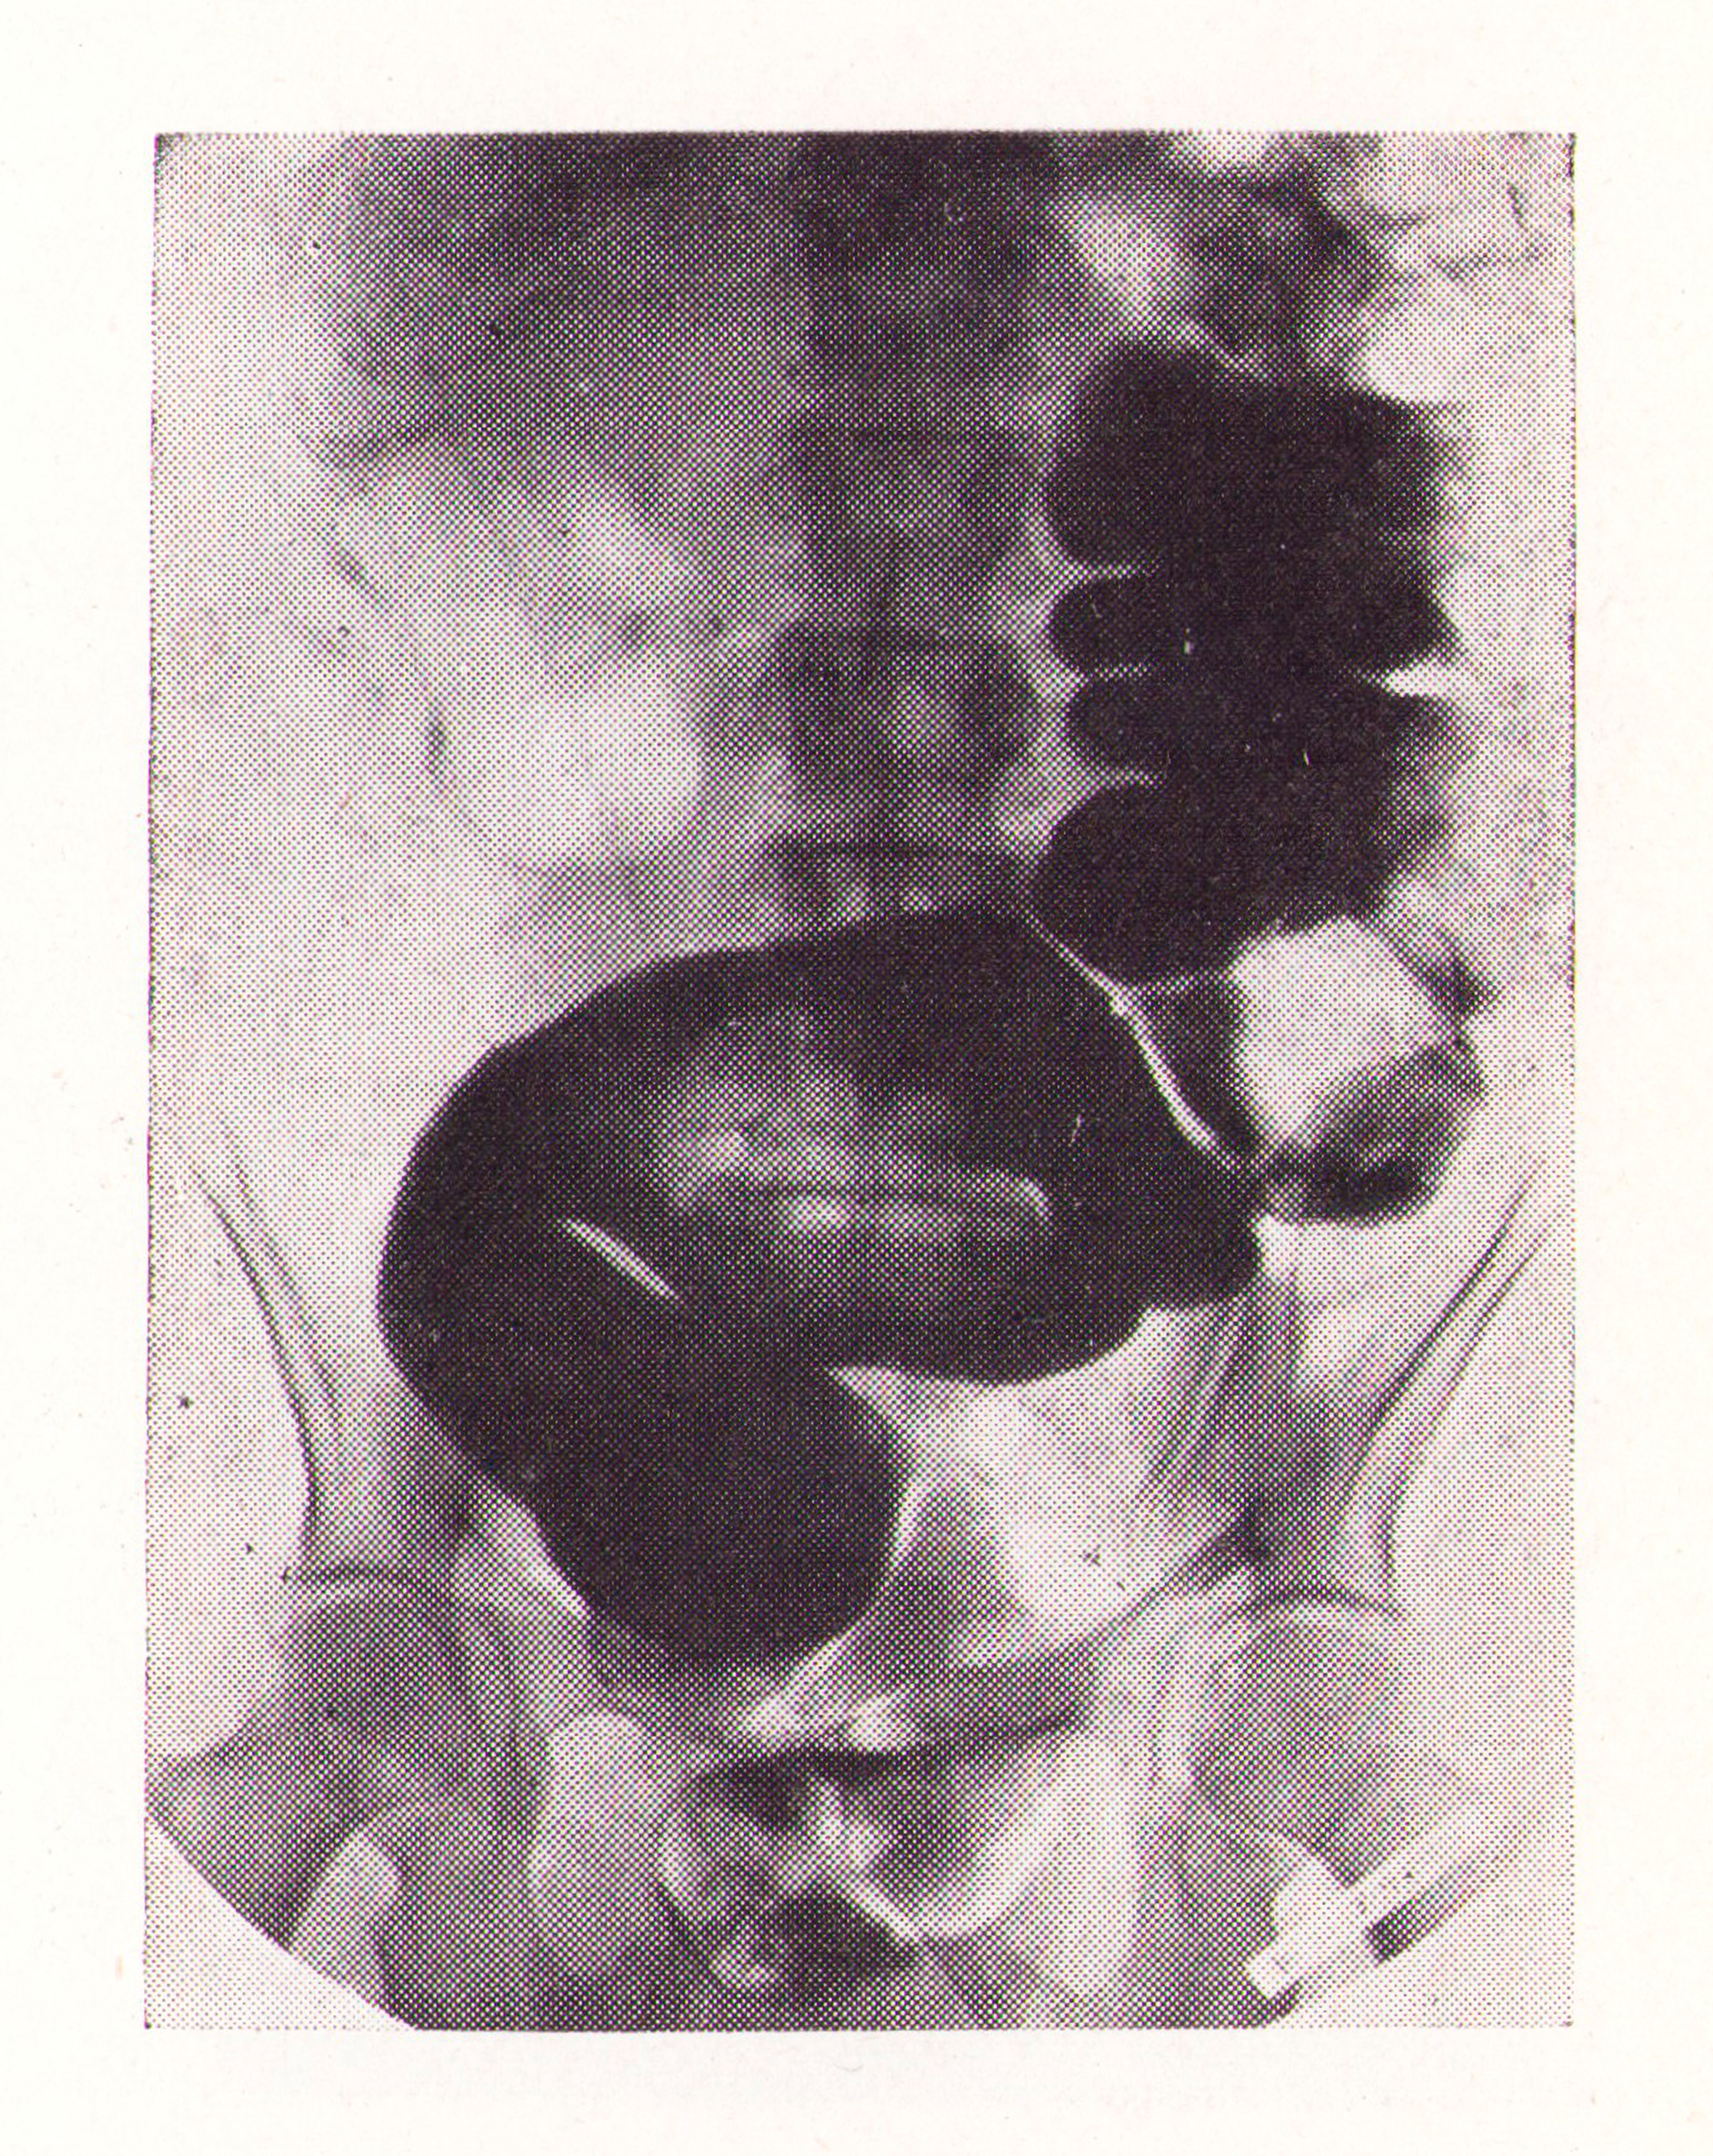

El bario rodea el fecaloma en la ampolla rectal.

Fig.2. Revista Española de ciencias médicas, Clínica y laboratorio, 1953.